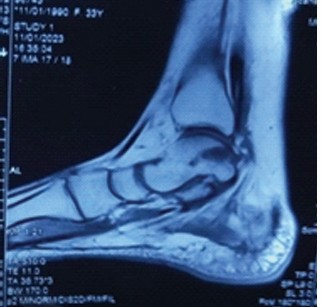

Assessment of Functional Outcome of Arthroscopic Microfractures for Osteochondral Defect of Talus

Lionel John , G Manikandan